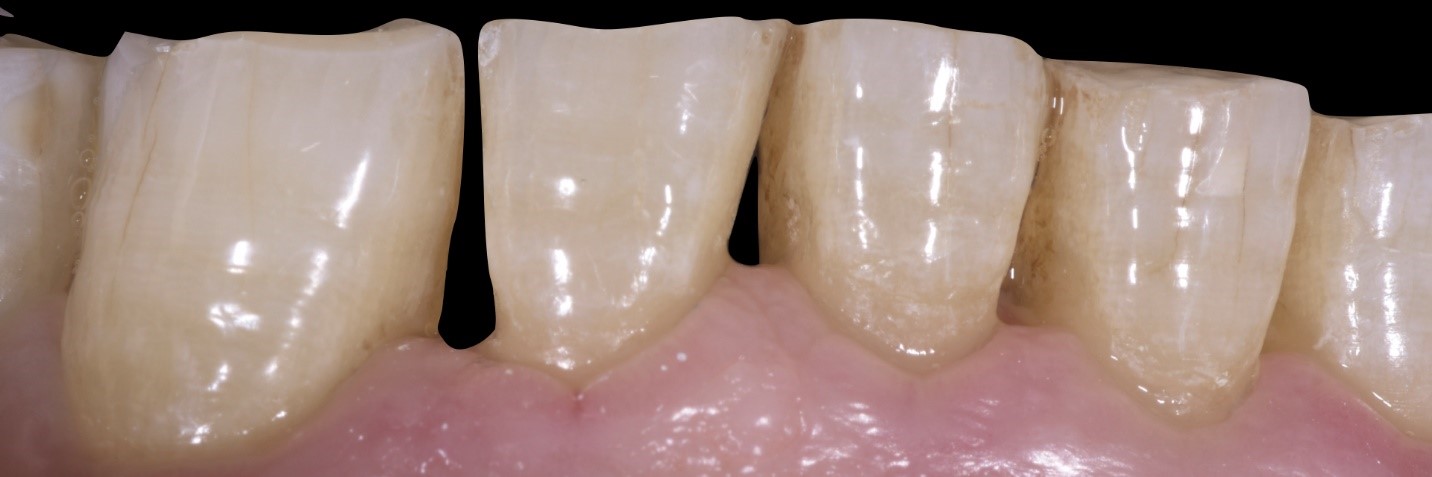

garrison-roberto-turrini

Fig. 3

Si noti la quantità di smalto residua che, anche negli elementi dentali maggiormente coinvolti, permette l’impiego di tecniche adesive con minima preparazione dentale ( tecnica MIPP, Minimally Invasive Prosthetic Procedure, by Fradeani Education).